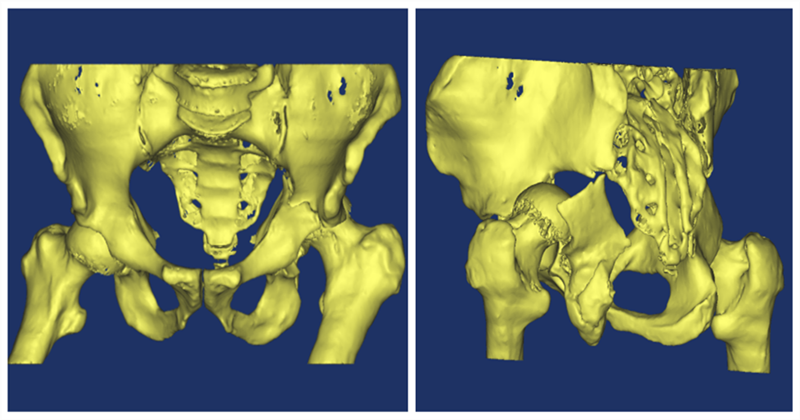

病例介绍:患者李X,男性,60岁,因“车祸致左髋部外伤3小时,疼痛、活动受限”入院,左踝及左足踇趾背伸不能,左小腿外侧及左足背皮肤感觉迟钝,提示左侧坐骨神经损伤。行CT+三维成像提示:髋臼骨折(左),髋关节脱位(左)。急诊行左髋关节脱位手法复位,左股骨髁上骨牵引。并于伤后第7日行左髋臼骨折切开复位内固定术。

术前在刘利主任带领全科医生针对该病例进行了术前讨论,制定手术计划。张洪彬主管医师利用MIMICS影像软件对患者的CT数据进行了提取,并进行重新建模,在得到三维图像后,切割、分离得到单独的髋臼影像。大家通过360°全方位对该病例三维影像进行研讨、观摩,初步制定手术计划为K-L入路行后壁骨折复位,钢板螺钉固定,前柱通道螺钉固定横行骨折。但是难点在于在没有手术导航的条件下如何精准打入髋臼前柱通道螺钉。

(入院时三维重建图像)

(伤后行髋关节复位三维重建图像 )